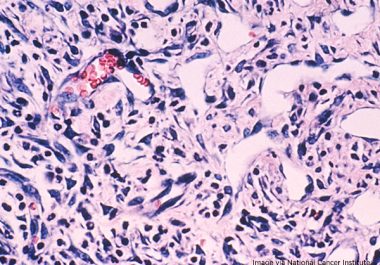

The FDA approved a combination of two immune checkpoint inhibitors to treat adult patients with unresectable malignant pleural mesothelioma....